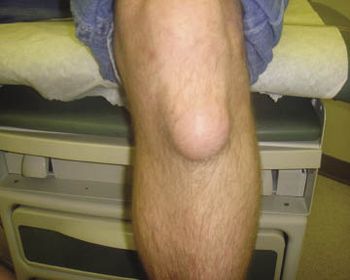

Injuries and overuse often are the cause of knee disorders, but chronic conditions also create problems. This week’s photo quiz offers several presentations to test your knowledge.